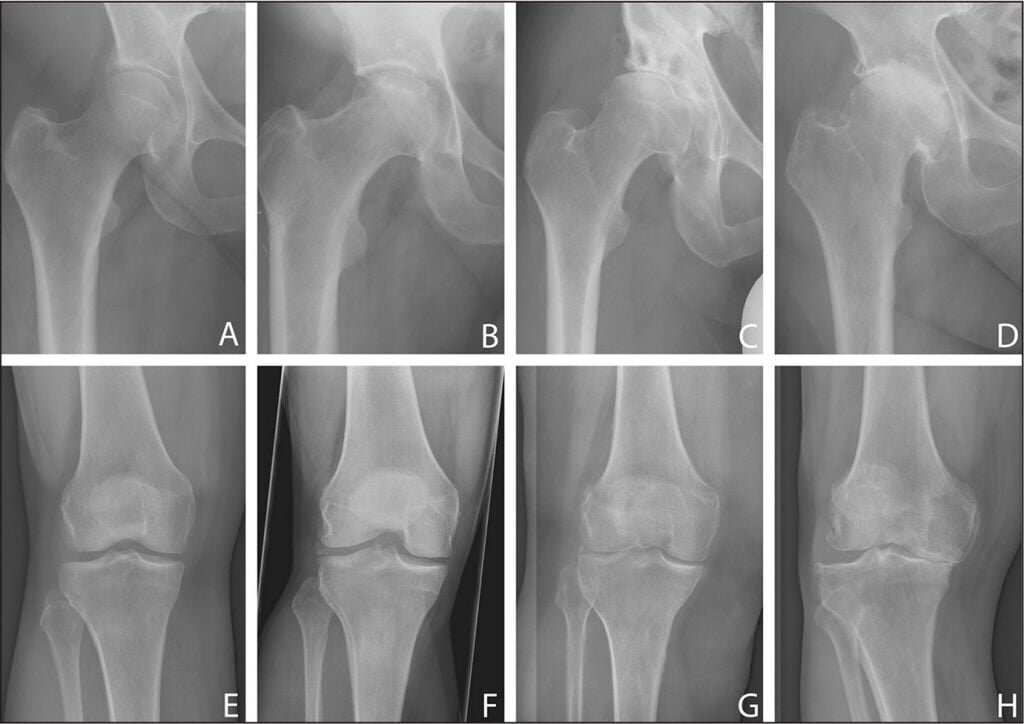

🟢 Рентгенография - самый простой и достоверный метод обнаружения сужения суставной щели и костных выростов (остеофитов).